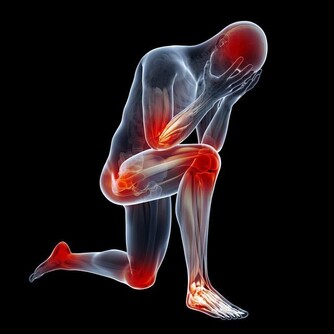

4、骨骼強壯:中醫認為,腎主骨,骨靠腎精滋養,腎好骨才好。腎氣衰敗會出現骨質疏鬆、腰酸背痛,甚至牙齒出現鬆動。

第4名:過度勞累

首先是體勞,強度較大的工作導致身體疲勞,從而引發腎虛症狀。

其次是勞神,巨大的工作壓力和生活壓力導致精神無法放鬆,腦力勞動累,想得過多,也容易傷腎。